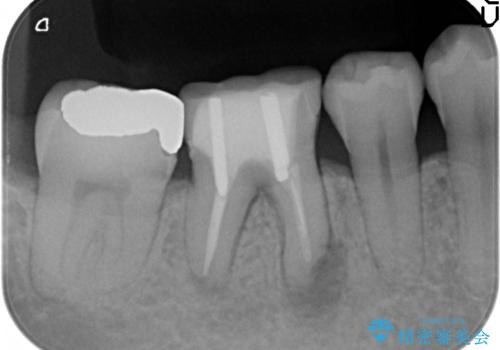

- 数か月前から右下の奥歯の歯茎から膿が出る、他院で相談したところ抜歯といわれたが何とか残せないか診て欲しいといらっしゃった方の症例です。

再根管治療を行い、フィステル(膿の出口)の消失および根尖病変の縮小を確認後、オールセラミッククラウンによる補綴を行いました。